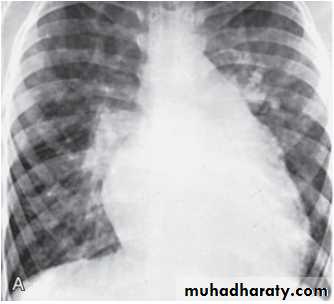

CXR : Boot-shaped normalsize heart

CXR : Egg on side & narrow mediastinum